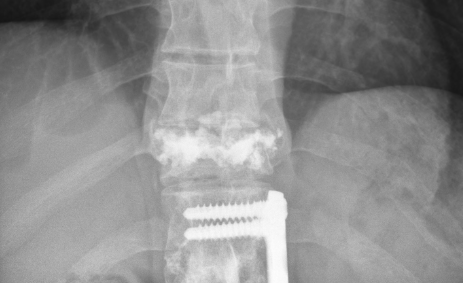

It’s been about a month since the doctors were able to perform a pretty miraculous procedure on my back. The accident burst my T11 vertebrae and since I already have a fusion and plates from T12-L2 the initial diagnosis was that to keep the spine supported they were going to have to fuse from T9 or T10 all the way down to L3 or L4 with the addition of rods/plates going from top to bottom of those locations. I told Dr. Sipos that I would prefer not to have such an invasive surgery and if he had any other options, initially he said that there was to much damage and that this was going to be the most feasible option, so I asked him to take a day or so and see if he could come up with any other options. He came to me the next day and said he had one other option of (for lack of better terminology) cementing the T11 vertebrae, removing all the extra bone fragments, and grinding down the portions that were pressuring the spine. It was not certain that it would work because of the amount of current injury and past injury, so he asked if I would like to take that option but if when he was performing the surgery he was not able to complete that option he had my permission to go with the full fusion from top to bottom as explained above. Of course I agreed and hoped for the best.

Needless to say his amazing talent worked out and he was able to perform the rebuilding of that vertebrae without having to insert and extra metal or fusions. Here are some pictures of what he was able to do and my current back.